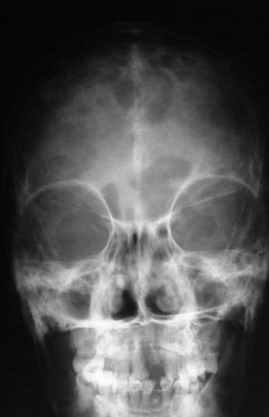

Уажаемые коллеги,представленные рентгенограмммы я показывал на нашем х-рей митинге - они были встречены с большим интересом.. Ну, ещё бы - я сам эту патологии встречал раза три за всю свою долгую жизнь:

После меня выступал с новыми находками для своей коллекции Эмануэл Лакью Тесема, хирург-ортопед из Эфиопии: Мне понравились его находки:

Кто шустрый - при какой патологии встречается так называемые "суставы Шарко"?Второе приобретение доктора Эмануэла мне понравилось своим романтическим названием: Candle bone - <кость-в-виде-оплывающей-свечи> : Просто редкая патология:

VR> Кто шустрый - при какой патологии встречается так называемые <суставы Шарко>?

Сирингомиелия,

Травма спинного мозга

Опухоль

Ленар Рашитов

Т.н. нейрогенная артропатия бвает при диабете, периферических нейропатиях, заболеваниях спинного мозга... Как-то довелось вести больного с таким поражением тазобедренных суставов при третичном сифилисе.